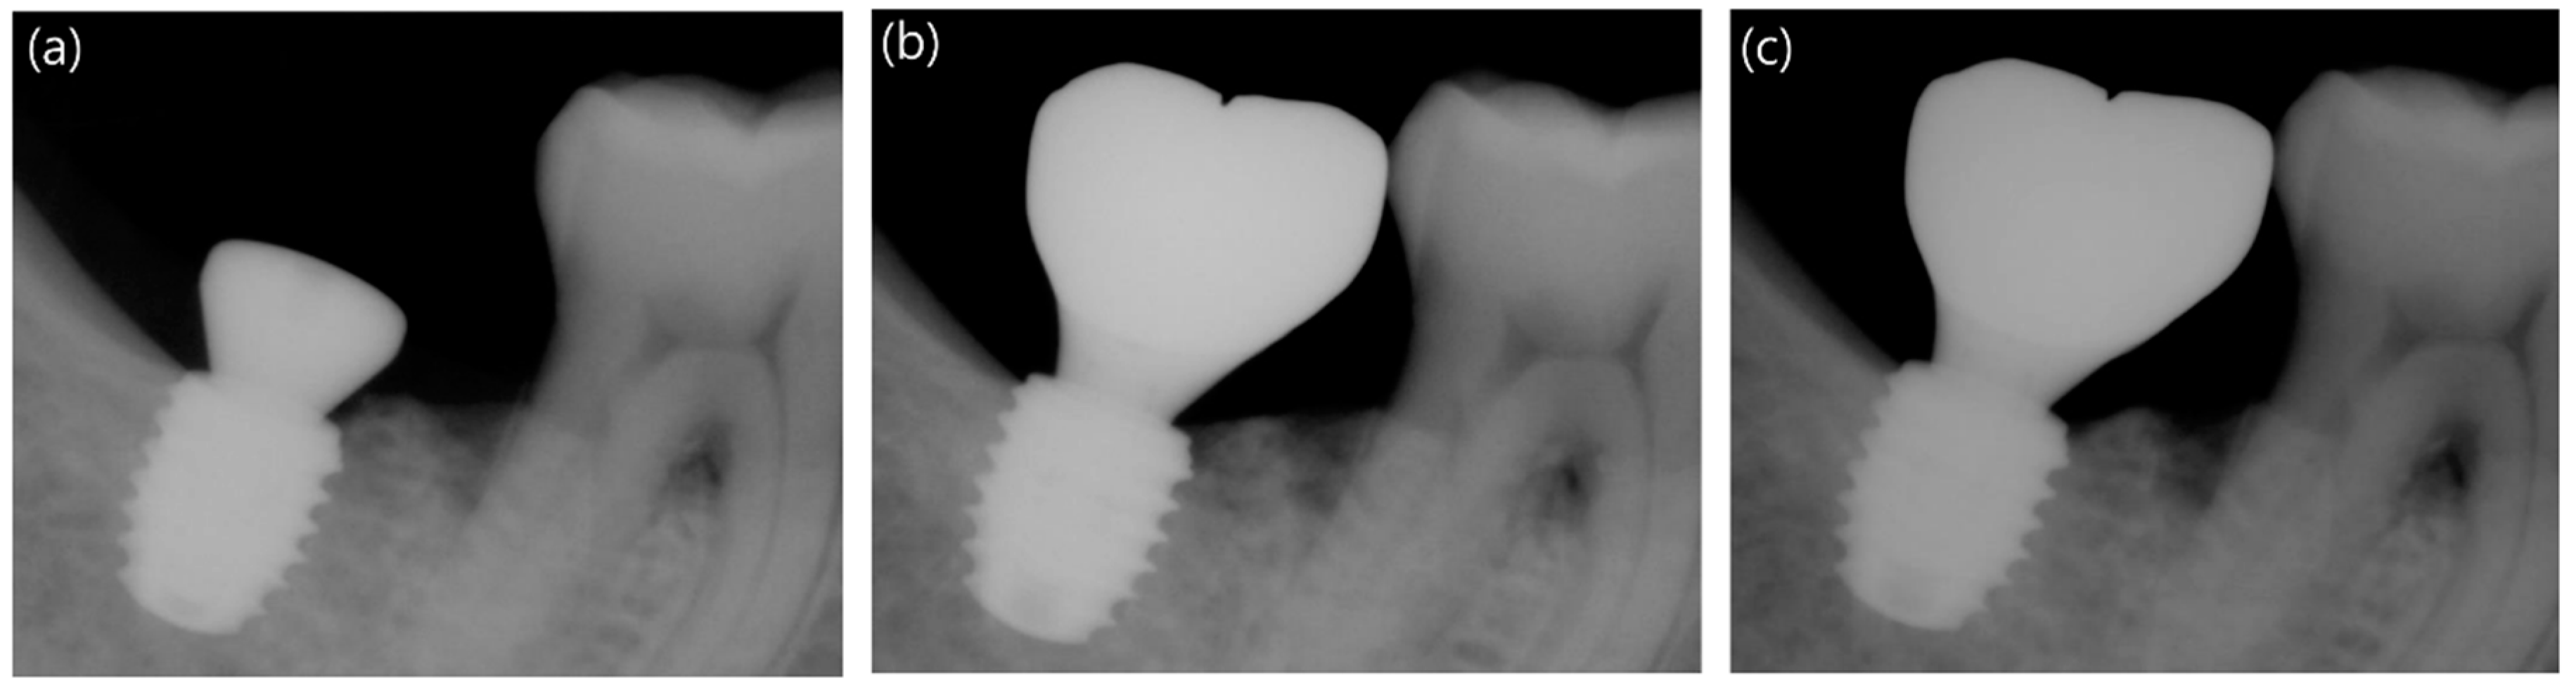

2.3.5. Measurement of Marginal Bone Loss

3.4. Comparison of Marginal Bone Loss between the Long and Short Implants

| 12-week follow up | Mesial | −0.22 ± 0.98 | -0.15 ± 0.79 | 0.893 |

| Distal | 0.08 ± 0.81 | 0.20 ± 0.78 | 0.728 | |

| Avg. | −0.07 ± 0.78 | 0.03 ± 0.63 | 0.885 | |

| 48-week follow up | Mesial | −0.15 ± 0.94 | -0.13 ± 0.82 | 0.719 |

| Distal | 0.27 ± 0.80 | 0.23 ± 0.92 | 0.573 | |

| Avg. | 0.06 ± 0.82 | 0.05 ± 0.77 | 0.655 | |